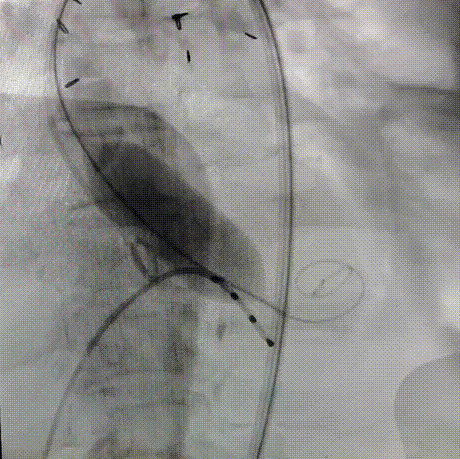

180bpm下置入23mm球囊扩张,沿导丝入26mm 爱德华经导管人工瓣膜输送系统,仔细定位,180bpm下释放瓣膜。释放后血压低,起搏心率,复查主动脉根部造影,轻度反流,LCX可疑血流不好,沿导丝入EBU3.25到位,造影冠脉血流通畅,复查术中食道心超,人工瓣膜位置满意,开放良好,压差3mmHg,轻度反流。手术圆满结束。

释放瓣膜

术后主动脉造影